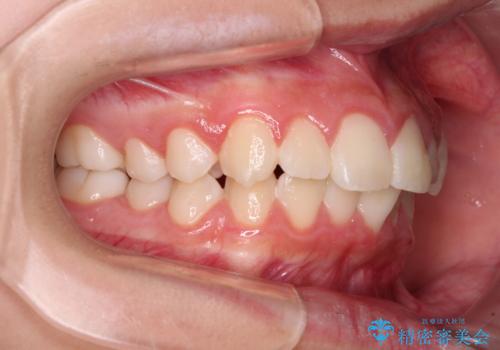

- 口元の突出感で口が閉じにくいとのことで来院された患者様です。

上下左右の第一小臼歯4本を抜歯し、ワイヤー装置での抜歯矯正を行うこととしました。

右側の咬み合わせは、上顎がやや前方位にある状態であったので、通常は補助装置を併用するのですが、高校生ということで補助装置なしで治療を行うこととしました。

口元の突出感が解消され、睡眠時の口呼吸が改善されました。